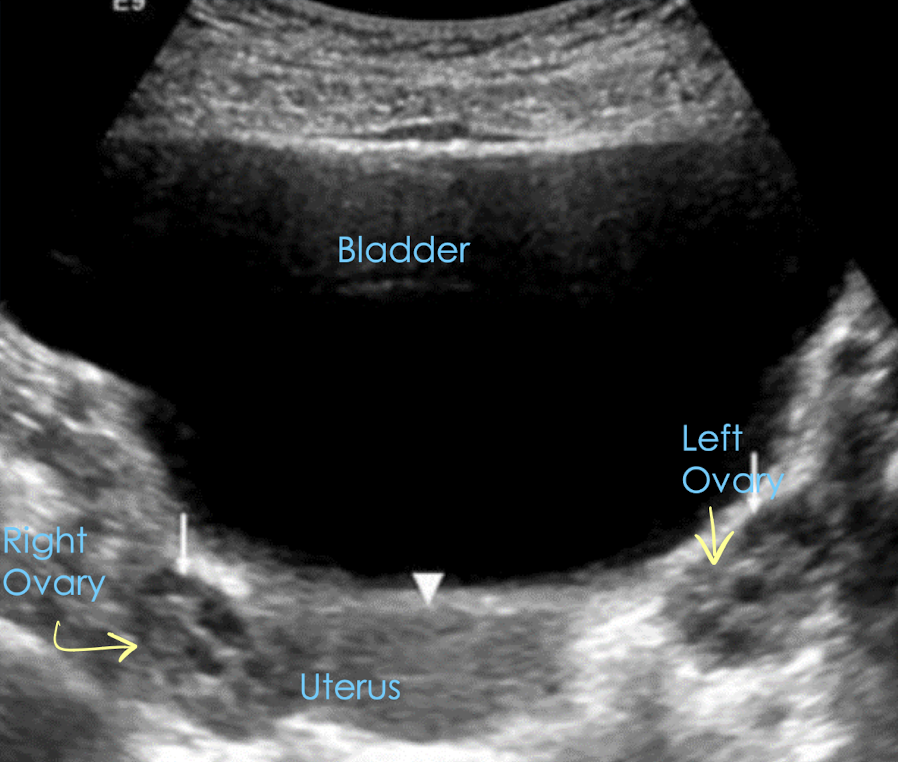

TA pelvic anatomy in TRANS

starting TRV is easiest way to find ovaries